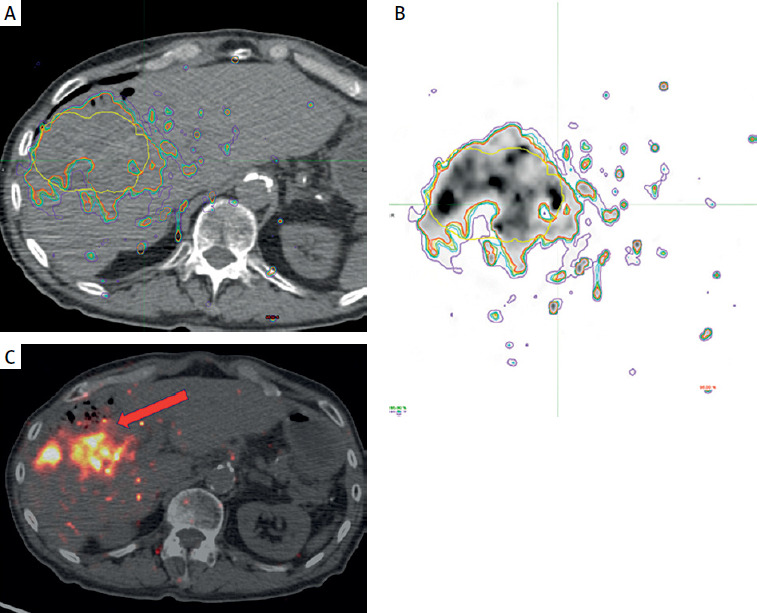

Three months after RL, the patient presented with fever and chills. Despite an infectious workup, imaging revealed a liver abscess secondary to a hepatocolic fistula (Figure 3). Intravenous antibiotics were administered, and a percutaneous drain was placed. Following a multidisciplinary team review, a right hepatectomy, fistulectomy, and colectomy were performed. Intraoperatively, a necrotic enteric wall with an abscess extending into the right liver lobe was identified. The patient was discharged on intravenous antibiotics 20 days after surgery with no signs of bacteremia.